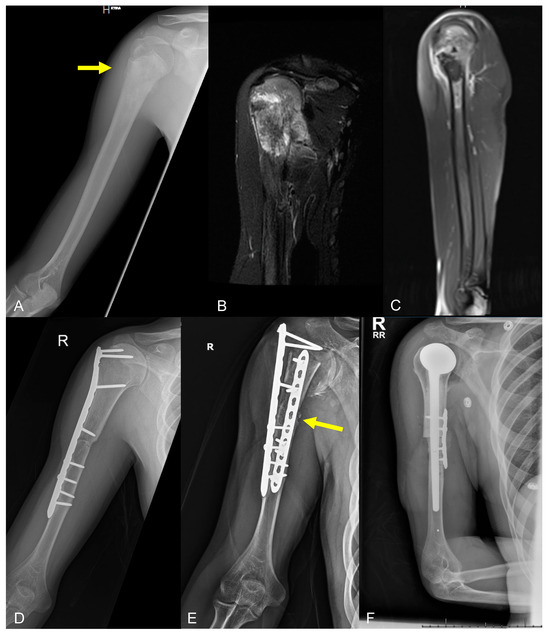

2.3.1. Structural Failure of Endoprostheses

- Type A: Fracture of an apophysis or protuberance of bone;

- Type B: Fracture involving the bed supporting or adjacent to an implant (B1, the implant is still well fixed; B2, the implant is loose; B3, the implant is loose and the bone bed is of poor quality);

- Type C: Fracture in the bone containing the implant but distant from the bed of the implant;

- Type D: Fracture affecting one bone which supports two replacements;

- Type E: Fracture involving two bones supporting one replacement;

- Type F: Fracture involving a joint surface which is not resurfaced or replaced but is directly articulating with an implant.